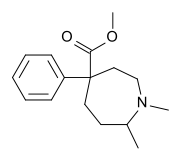

Phenylpiperidines

- Pethidine (meperidine)

The first fully synthetic opioid was meperidine (later demerol), found serendipitously by German chemist Otto Eisleb (or Eislib) at IG Farben in 1932.[228] Meperidine was the first opiate to have a structure unrelated to morphine, but with opiate-like properties.[199] Its analgesic effects were discovered by Otto Schaumann in 1939.[228] Gustav Ehrhart and Max Bockmühl, also at IG Farben, built on the work of Eisleb and Schaumann. They developed "Hoechst 10820" (later methadone) around 1937.[230] In 1959 the Belgian physician Paul Janssen developed fentanyl, a synthetic drug with 30 to 50 times the potency of heroin.[211][231] Nearly 150 synthetic opioids are now known.[228]